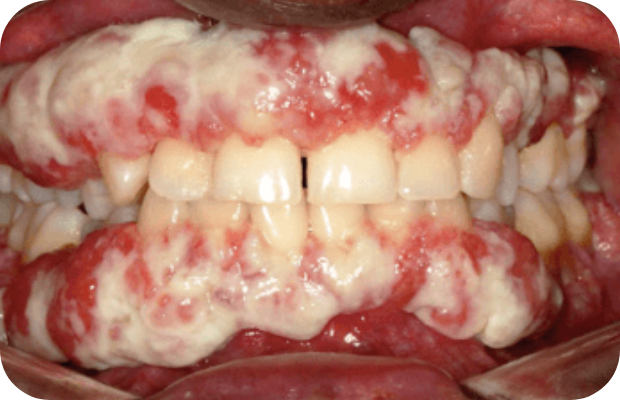

PLGD-1 lesion image gallery

Images of ligneous lesions in real patients with PLGD-1

2. Sadasivan A, Ramesh R, Mathew DG. Ligneous periodontitis in a patient with type 1 plasminogen deficiency: a case report and review of the literature. Case Rep Dent. 2020;2020:5680535.